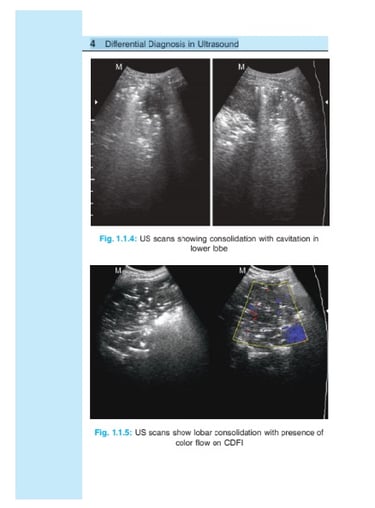

Differential Diagnosis in ULTRASOUND

Ultrasound is a noninvasive, relatively inexpensive and most rewarding imaging modality, carries no radiation

burden, but not much exploited for evaluation of chest disease because of basic (inherent) properties of US waves not to pass through bony cage and air-filled lungs. However, over a couple of years, US has emerged as a useful tool in evaluating wide range of perplexing clinical problems of chest due to presence of fluid in pleural space, consolidating or atelectatic lung or even tumor, provide window for US to penetrate and this has helped in diagnosis of certain conditions or limit the DD of conditions under consideration.